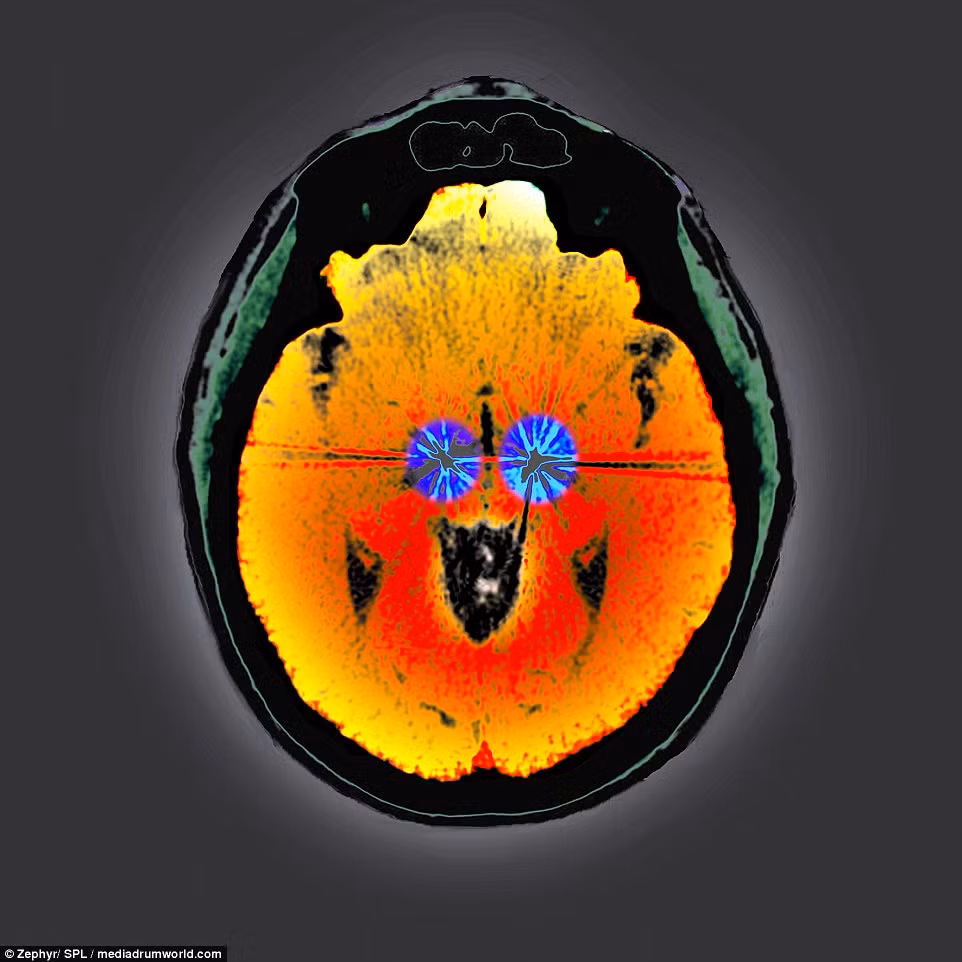

Đây là não của một bệnh nhân bị bệnh Parkinson. Hai cực điện của thiết bị kích thích não đã được cấy vào não để điều hòa nhịp tim. Thiết bị này gửi tín hiệu xung điện đến các vùng não màu xanh để cải thiện những triệu chứng của bệnh này.